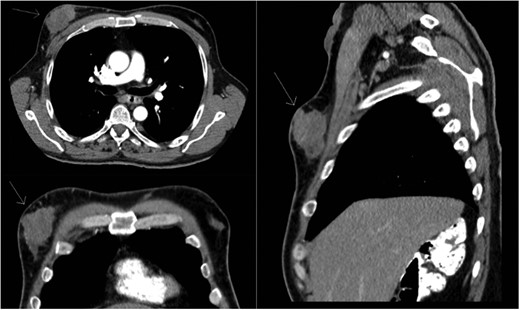

A 56-year-old male presented with a right-sided breast mass confirmed on mammogram as a 5.4 × 4.4 cm lobulated solid mass suspicious for cancer (Fig. 1). Axillary ultrasound revealed one suspicious lymph node. Core needle biopsy of the breast mass showed invasive poorly differentiated ductal carcinoma, ER+/PR+/HER+. The lymph node biopsy was negative for malignancy. Medical history was significant for hypertension and neurofibromatosis type 1. The patient noted no family history of breast, ovarian or prostate cancer; however, there was a four generation history of neurofibromatosis on his mother's side.

Right chest wall neurofibroma. Breast cancer is superior to the nipple.